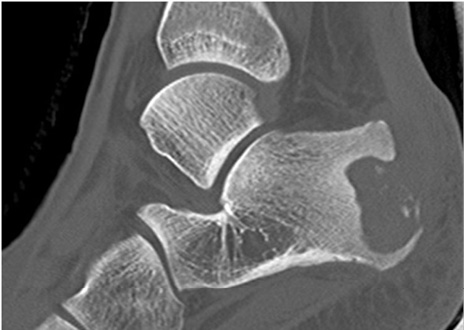

La radiografía convencional fue examen de rutina en todos los pacientes del estudio. Evidenció hallazgos inespecíficos en 5 de 9 pacientes consistentes en edema de tejidos blandos. En uno de esos casos se apreciaron lesiones óseas en el calcáneo (Figura 1). La TC se utilizó como complemento en un caso para confirmar un defecto óseo cortical secundario a la infección (Figura 2).

Figura 2. Corte sagital de una TAC en una paciente de 15 años con osteomielitis de calcáneo. Se observa una lesión lítica extensa en el aspecto posterolateral, con secuestros en su interior, y otro foco de lisis en la parte anterior del calcáneo. Imágenes propias de los autores